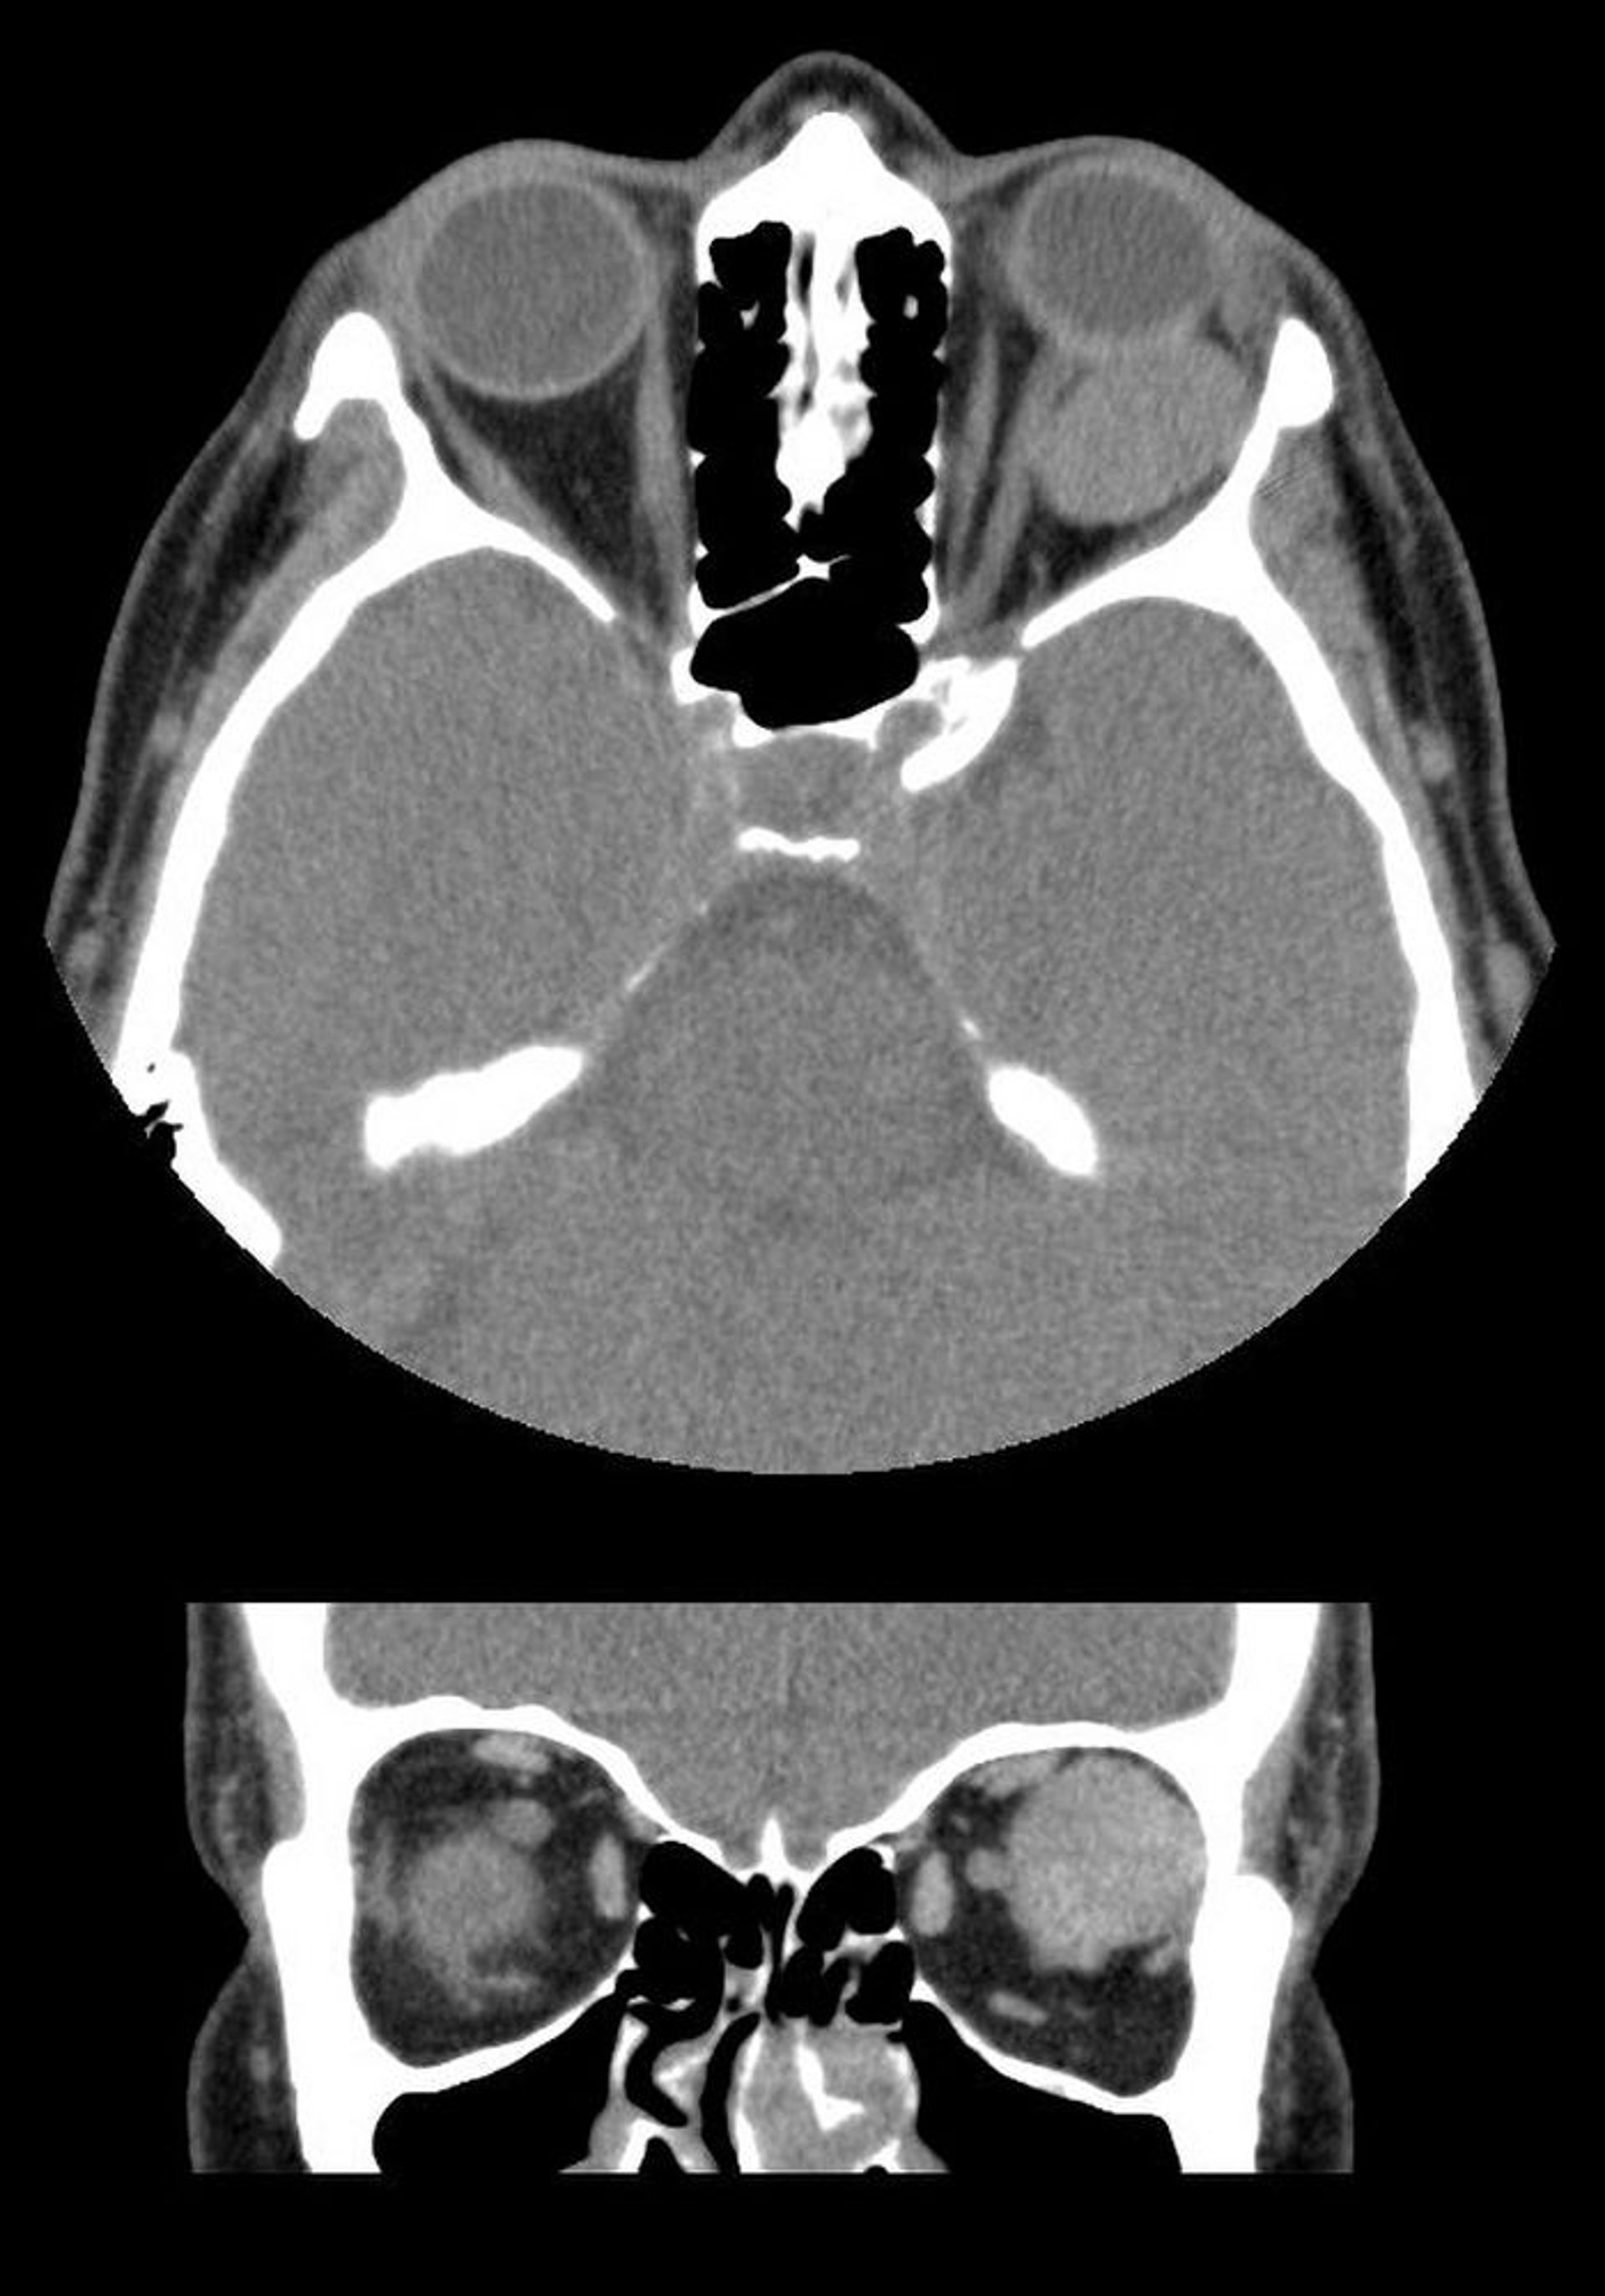

Trong hình ảnh này, chụp CT cắt lớp trục (trên) và xung quanh (dưới) cho thấy một khối nội tạng được phân chia rõ ràng phía sau quả cầu bên trái. Khối này là một dị dạng tĩnh mạch hang.

Hình ảnh do bác sĩ James Garrity cung cấp.